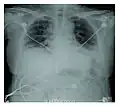

Rapid progression from initial symptoms to respiratory failure is a key feature. An X-ray that shows ARDS is necessary for diagnosis (fluid in the small air sacs (alveoli) in both lungs). In addition, a biopsy of the lung that shows organizing diffuse alveolar damage is required for diagnosis. This type of alveolar damage can be attributed to nonconcentrated and nonlocalized alveoli damage, marked alveolar septal edema with inflammatory cell infiltration, fibroblast proliferation, occasional hyaline membranes, and thickening of the alveolar walls. The septa are lined with atypical, hyperplastic type II pneumocytes, thus leading to the collapse of airspaces. Other diagnostic tests are useful in excluding other similar conditions, but history, X-ray, and biopsy are essential. These other tests may include basic blood work, blood cultures, and bronchoalveolar lavage.